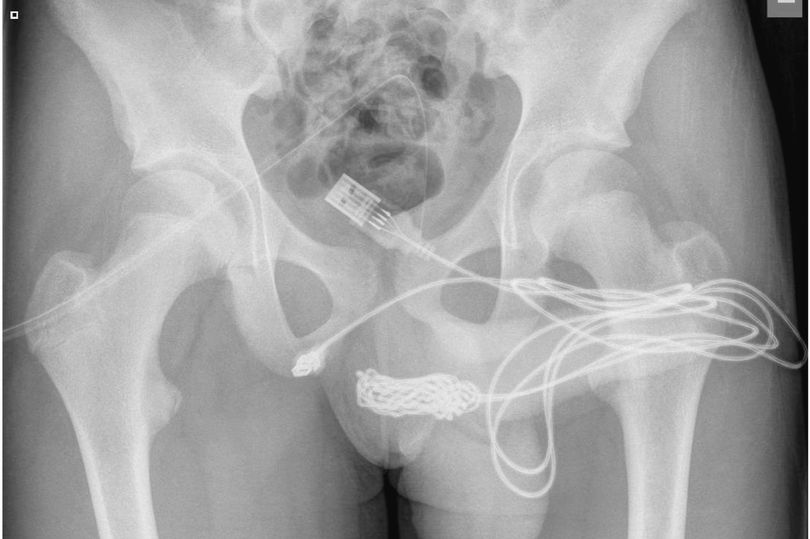

醫師照X光發現,不僅體內有明顯的USB傳輸線影像,整條線甚至打結,糾結在一起。最後少年被轉往倫敦大學醫學院進行手術,醫師將少年的生殖器周圍肌肉切開,並逐步把傳輸線打結之處切除,最後成功將傳輸線取出。